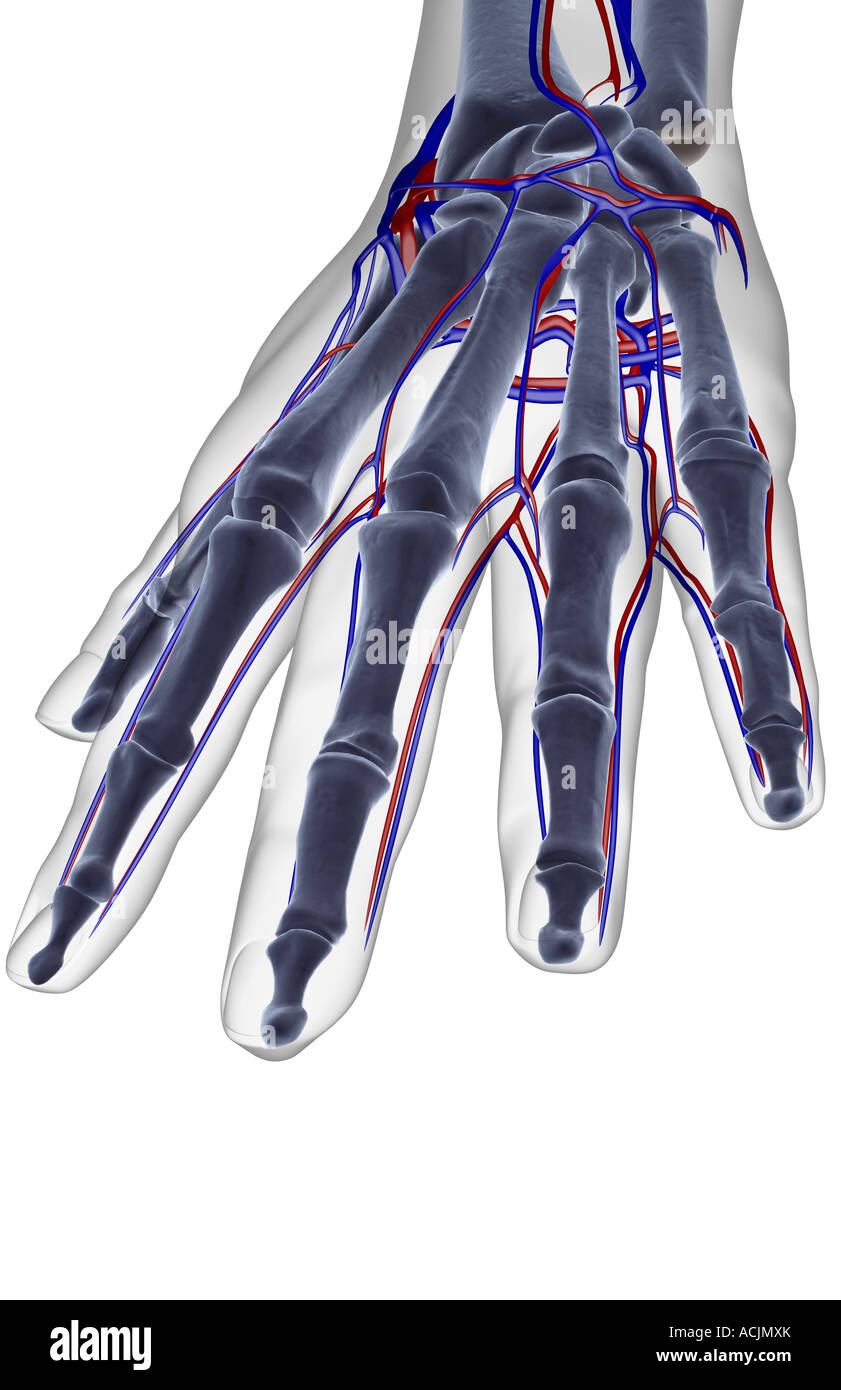

The blood supply of the hand Stock Photohttps://www.alamy.com/image-license-details/?v=1https://www.alamy.com/stock-photo-the-blood-supply-of-the-hand-13171962.html

The blood supply of the hand Stock Photohttps://www.alamy.com/image-license-details/?v=1https://www.alamy.com/stock-photo-the-blood-supply-of-the-hand-13171962.htmlRFACJMXK–The blood supply of the hand